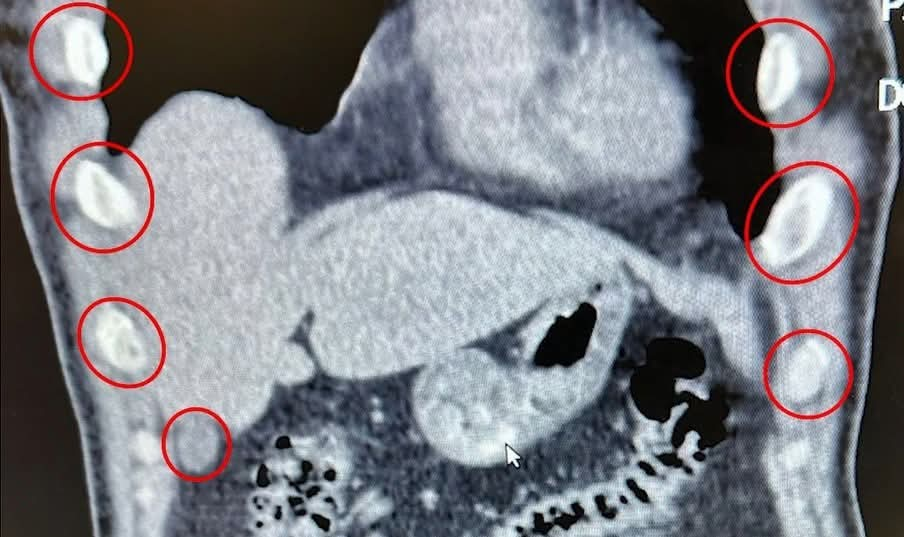

Yapılan operasyonla, iki şüphelinin midesinden 136 adet kapsül içerisinde, toplam 1 kilo 48 gram metamfetamin maddesi ele geçirildi.